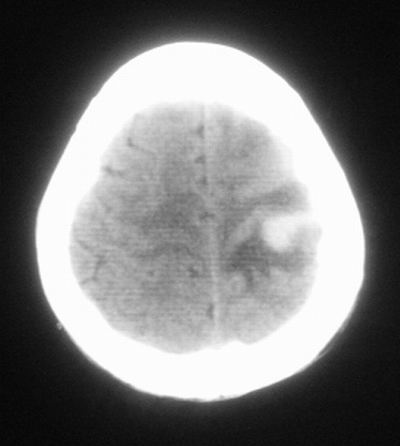

患者,男,30岁,右侧面部麻木,右上肢活动受限27小时。pe:神清、呼吸平稳,口角左歪,右上肢活动受限,右手掌握力消失,右侧躯体痛觉减退。

第一次颅脑ct扫描:左侧额顶叶血肿。